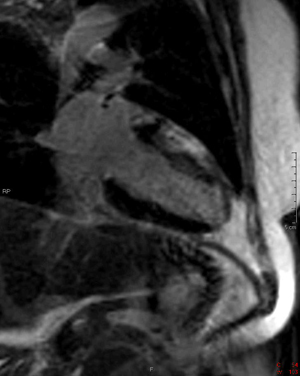

4) What are the primary physiologic consequences of the entity in the image shown below?